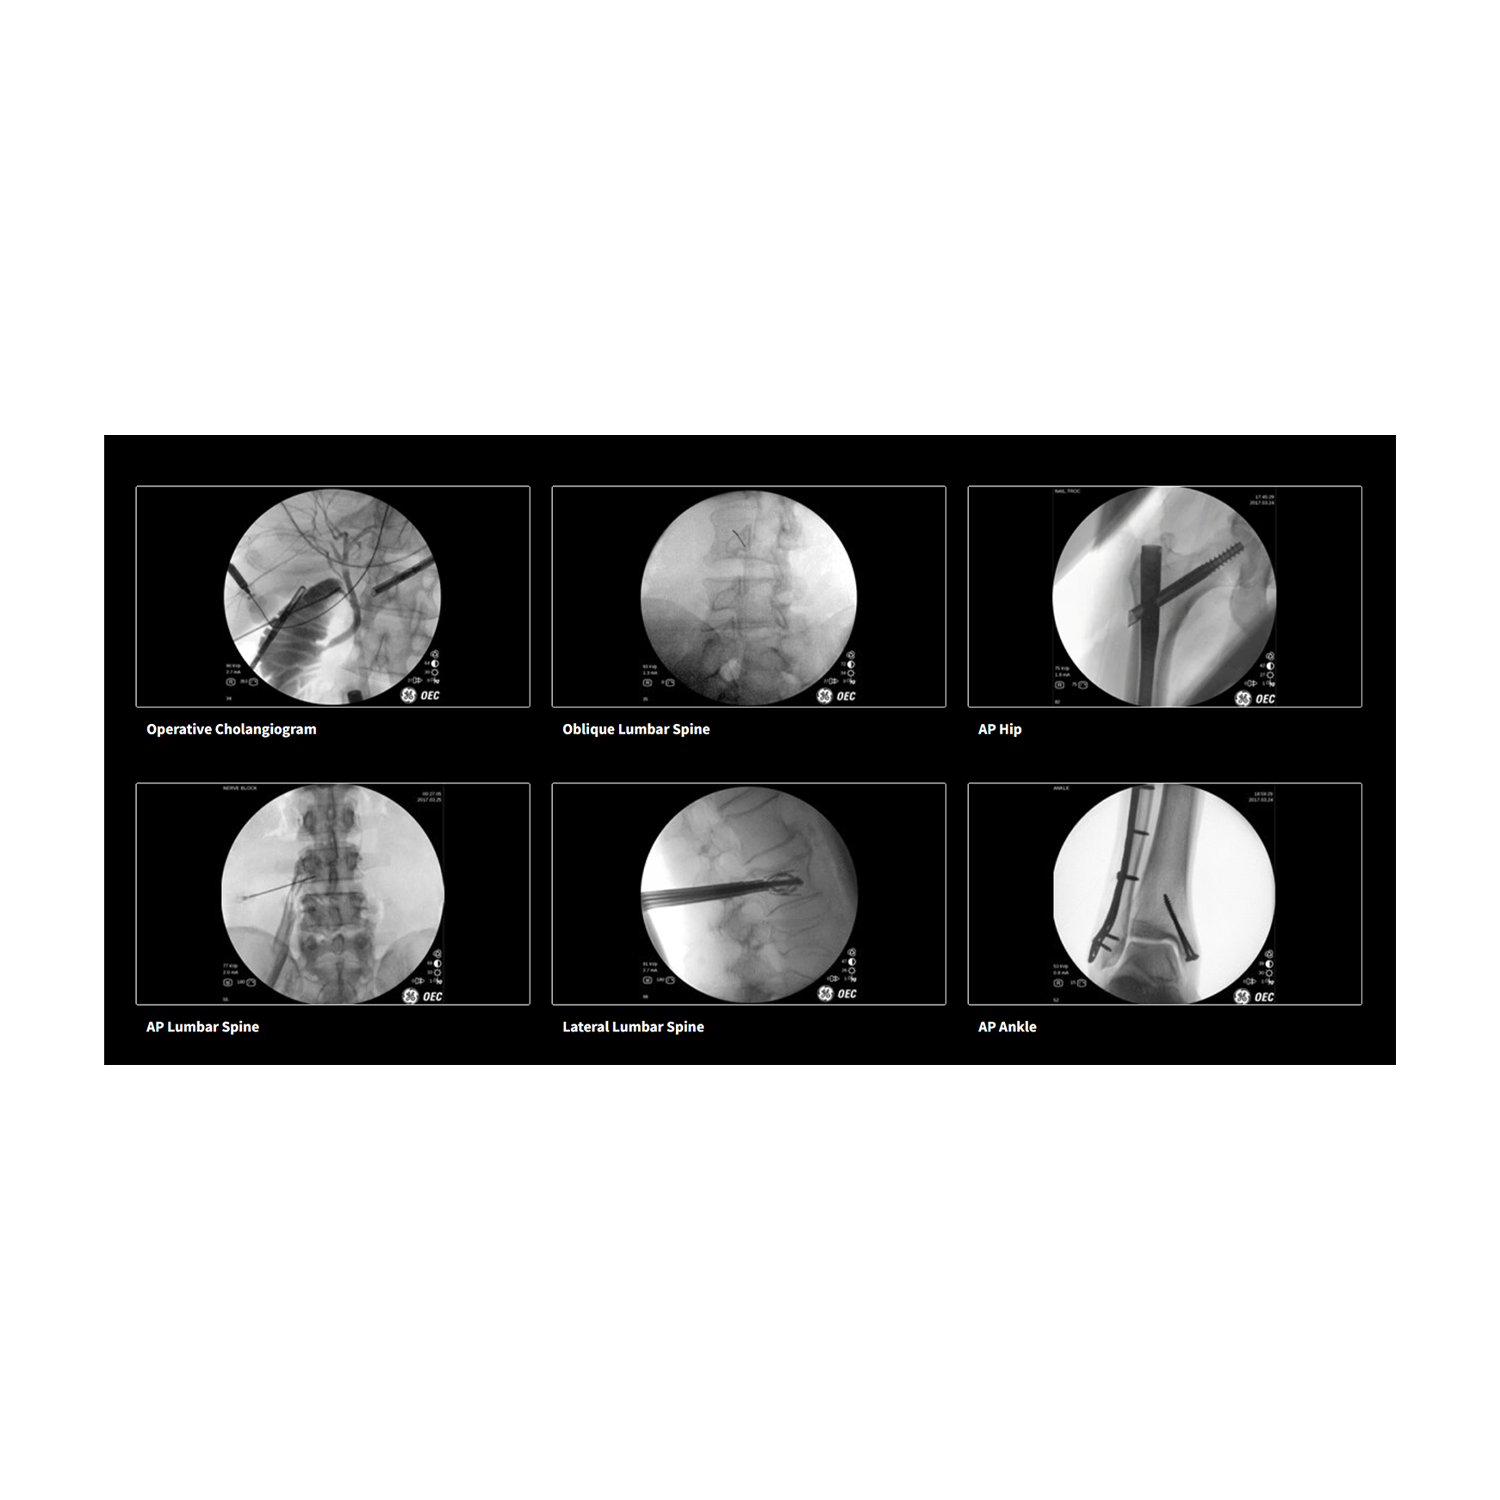

The GE Healthcare OEC One is a comprehensive C-arm system designed to deliver high-quality, Clear View images tailored to the user's needs in various clinical settings. It offers enhanced visibility and the ability to quickly adjust images on the fly.

The OEC One comes in three distinct configurations. The Standard Offering features intelligent automatic software that senses anatomy to provide optimal imaging at the right mA and kV settings. The PM Care Offering is tailored for pain management, providing precise anatomical localization and recording needle positions with real-time digital subtraction angiography (DSA) and cine capabilities up to 8 frames per second. The Vascular Offering is designed for detailed visualization in peripheral vascular and thoracic procedures, capable of highlighting fine details like a .014” guidewire and the sharp edges of vessels during angiography with the aid of Roadmap technology.